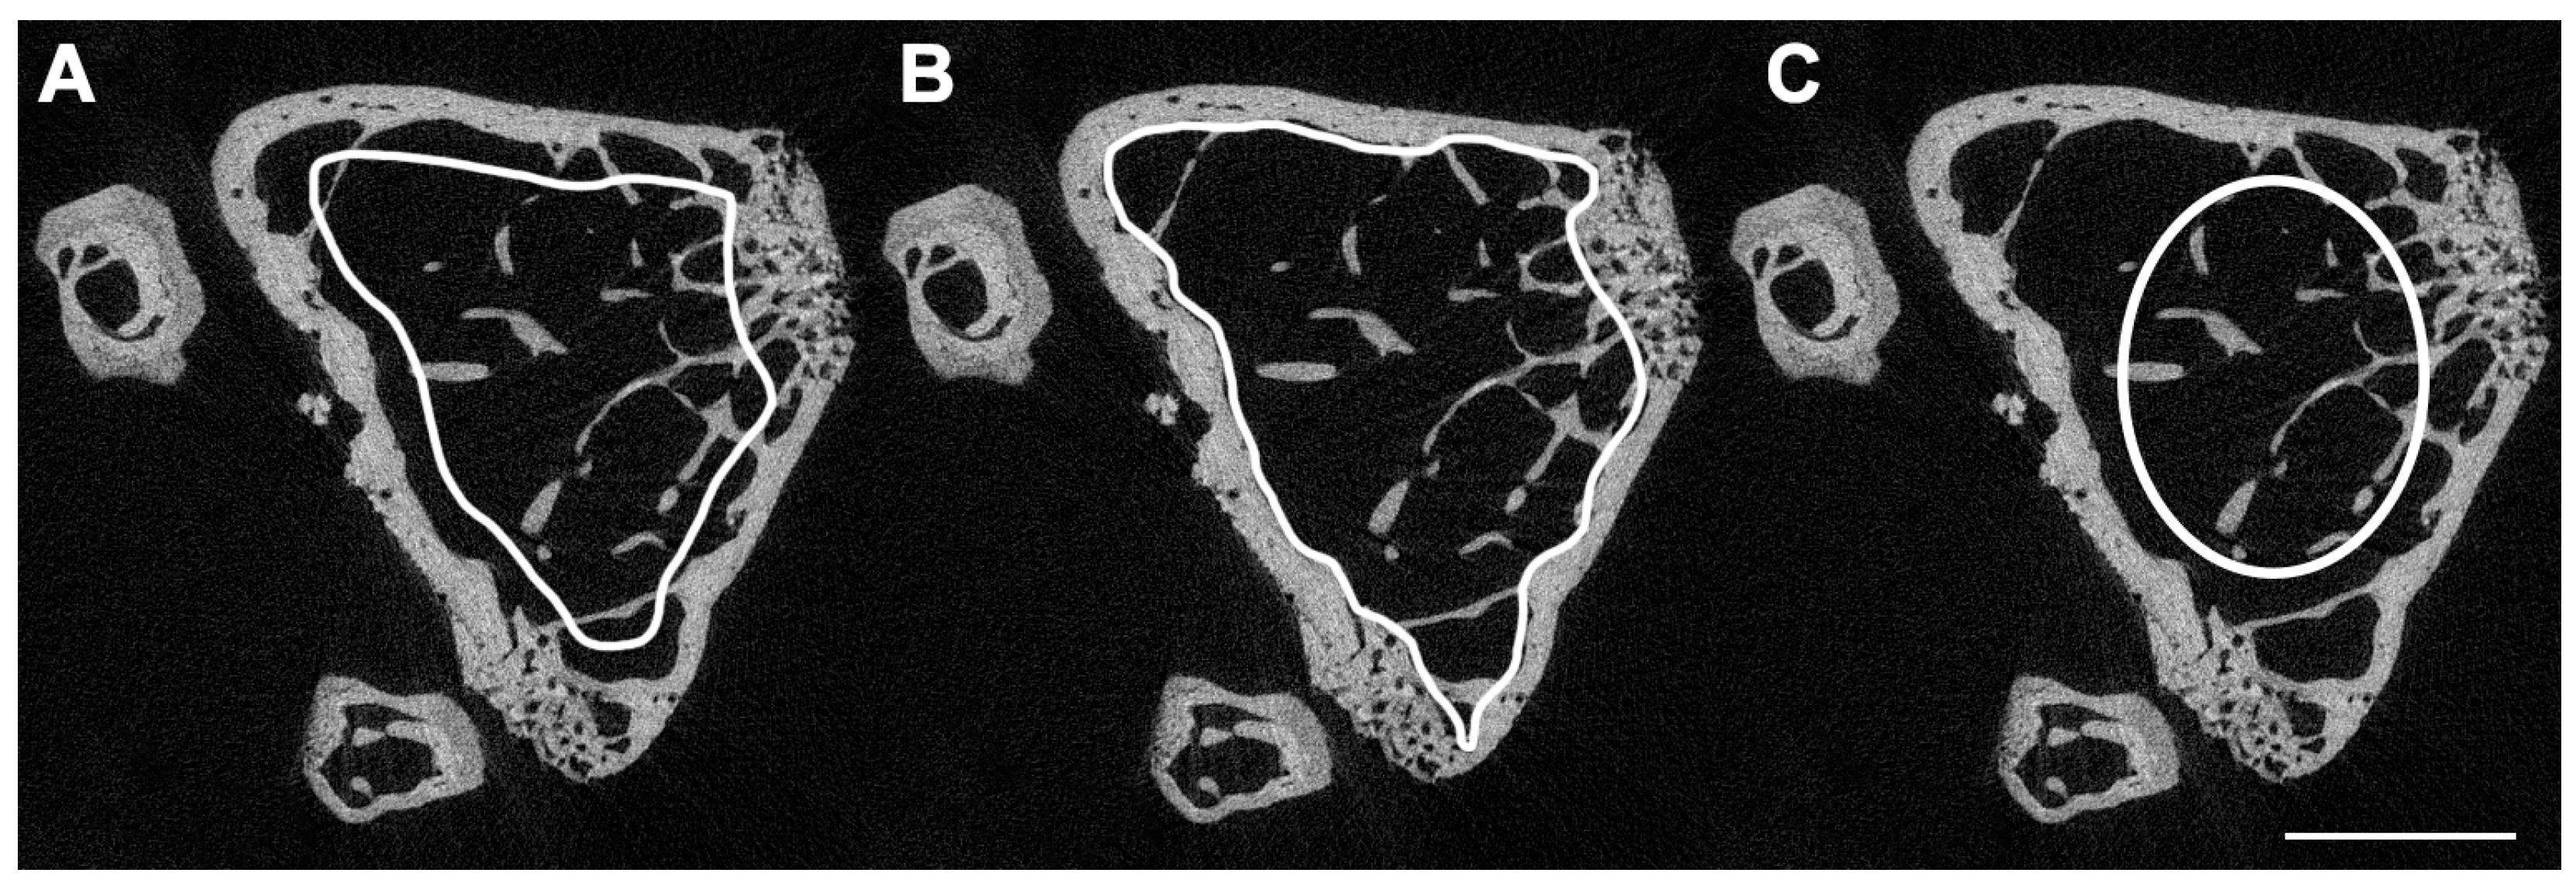

Another potential source of error is the incorrect delineation of volumes of interest (VOIs) to separate trabecular and cortical bone. For VOIs including trabecular bone, contours may be drawn manually a few voxels away from the endocortical surface and semi-automatically morphed across slices. The slices should then be visually inspected to ensure that the semi-automatic morphing contours have not drifted to include cortical bone. Other options include irregular anatomical contouring at the edge of the endocortical bone surface or a regular, uniformly shaped VOI, such as a cylinder or circle, delineated within the trabecular network (Figure 5).

Figure 5.

Three different contouring methods to delineate trabecular bone. (A) Irregular anatomical contouring a few voxels away from the endocortical bone surface. This method is more suitable when morphing the volume of interest (VOI) between slices and minimizes the need for slice-by-slice correction from “line drift” into cortical bone. (B) Irregular anatomical contouring at the very edge of the endocortical bone surface. This method ensures that all trabecular bone is encompassed in the VOI, but it increases the risk of cortical “line drift” when morphing between slices. (C) Regular and uniform, non-anatomical method to contour quickly and easily. A cylindrical VOI is contoured in the middle of the trabecular-rich region of interest. A disadvantage of this method is that a substantial amount of trabecular bone is outside the VOI. Image acquired at 3.5 μm, 55 kVp, 145 mA, and 800 ms integration time (μCT 35, Scanco Medical, Wangen-Brüttisellen, Switzerland). Scale bar = 100 μm.